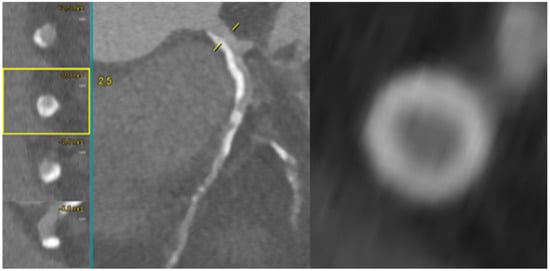

Coronary CT Angiography for PCI Planning and Guidance: A Comprehensive Narrative Review

by Lorenzo Fargione, Pietro Laforgia, Thomas Hovasse, Bernard Chevalier, Nicolas Amabile, Francesca Sanguineti, Stephane Champagne, Thierry Unterseeh, Antoinette Neylon, Neila Sayah, Jerome Garot, Lisa Simioni, Mario Togni, Stephane Cook, Hakim Benamer, Livio D’Angelo, Philippe Garot, Mariama Akodad and Ioannis Skalidis

Coronary computed tomography angiography (CCTA) is increasingly recognized as a comprehensive tool for planning percutaneous coronary intervention (PCI). By integrating plaque morphology, calcium burden, and CT-derived coronary physiology, CCTA enables non-invasive assessment of lesion complexity and supports precision-guided revascularization. This narrative review synthesizes [...] Read more.

Coronary computed tomography angiography (CCTA) is increasingly recognized as a comprehensive tool for planning percutaneous coronary intervention (PCI). By integrating plaque morphology, calcium burden, and CT-derived coronary physiology, CCTA enables non-invasive assessment of lesion complexity and supports precision-guided revascularization. This narrative review synthesizes current evidence on CT-guided PCI from original studies, registries, expert consensus documents, and international guideline recommendations. The literature was identified through PubMed, Embase, and Google Scholar, focusing on CCTA-based plaque characterization, calcium assessment, bifurcation and ostial lesions, chronic total occlusions (CTO), FFR-CT, virtual PCI simulation, and fusion imaging. Particular attention was given to contemporary investigations such as SYNTAX III, P3, and the ongoing P4 trial. CCTA reliably characterizes stenosis severity, plaque distribution, and calcification, demonstrating strong concordance with intravascular imaging. CT-based measurements support accurate stent sizing, prediction of calcium modification requirements, and identification of high-risk features in bifurcation and ostial disease. In CTO PCI, CCTA enhances visualization of proximal cap morphology, occlusion length, tortuosity, and distal vessel quality, outperforming angiographic scoring systems. CT-derived physiology and virtual PCI planning improve lesion selection and allow prediction of post-PCI hemodynamics. Emerging technologies—including photon-counting CT, artificial intelligence-assisted plaque analysis, and CT–fluoroscopy fusion—further expand the applicability of CT-guided PCI. The ongoing P4 trial is expected to provide definitive validation of CT-guided PCI and may support its incorporation into routine clinical workflows. Full article